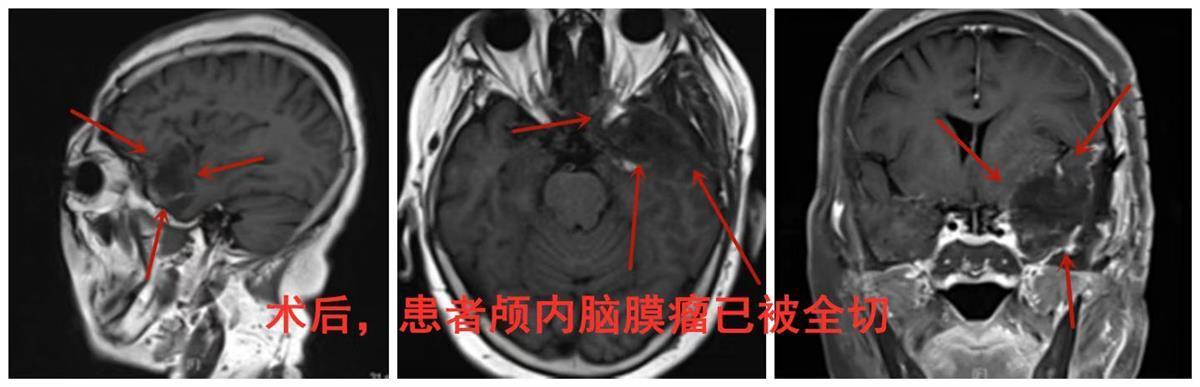

在患者及家属的信任和认可下,岑波带领手术医师郝鸣、尹都通过神经导航和B超的精准定位,锁定植根于颞极、血供丰富且与硬脑膜组织粘连的瘤体,成功全切脑瘤。术后,经两周精心医护,高婆婆未再发作癫痫,无遗留其他功能障碍,即将康复出院。

术后影像图